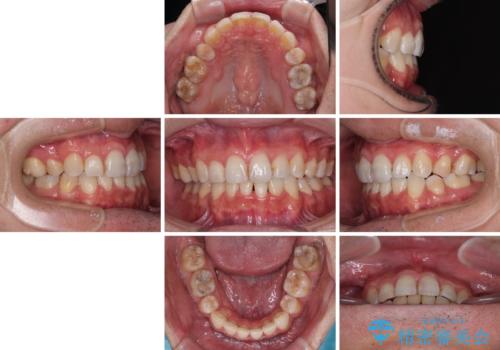

裏側装置での交叉咬合改善は非常に困難なもので、頻繁に装置の脱落がありました。

それでも想定以上に治療期間は長期化せず、咬み合わせも口元も満足のいく仕上がりとなりました。